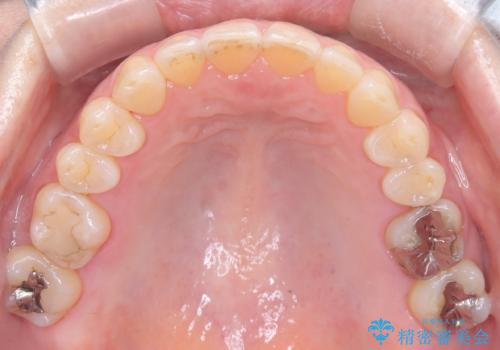

今回の矯正治療では、歯の色に近い目立たない審美ブラケットとワイヤーを使用しました。

スペース確保のために、まず奥歯全体をわずかに後方へ動かす遠心移動を実施し、前歯を並べるためのスペースを確保。さらに、安全性に配慮しながら歯の側面をわずかに削るIPRを併用し、デコボコを解消しました。

ワイヤー矯正ならではの確実な歯のコントロールにより、当初の計画通り約1年という短い期間で、前歯のガタつきが解消。見た目が美しく整っただけでなく、清掃しやすい機能的な歯並びを獲得していただけました。